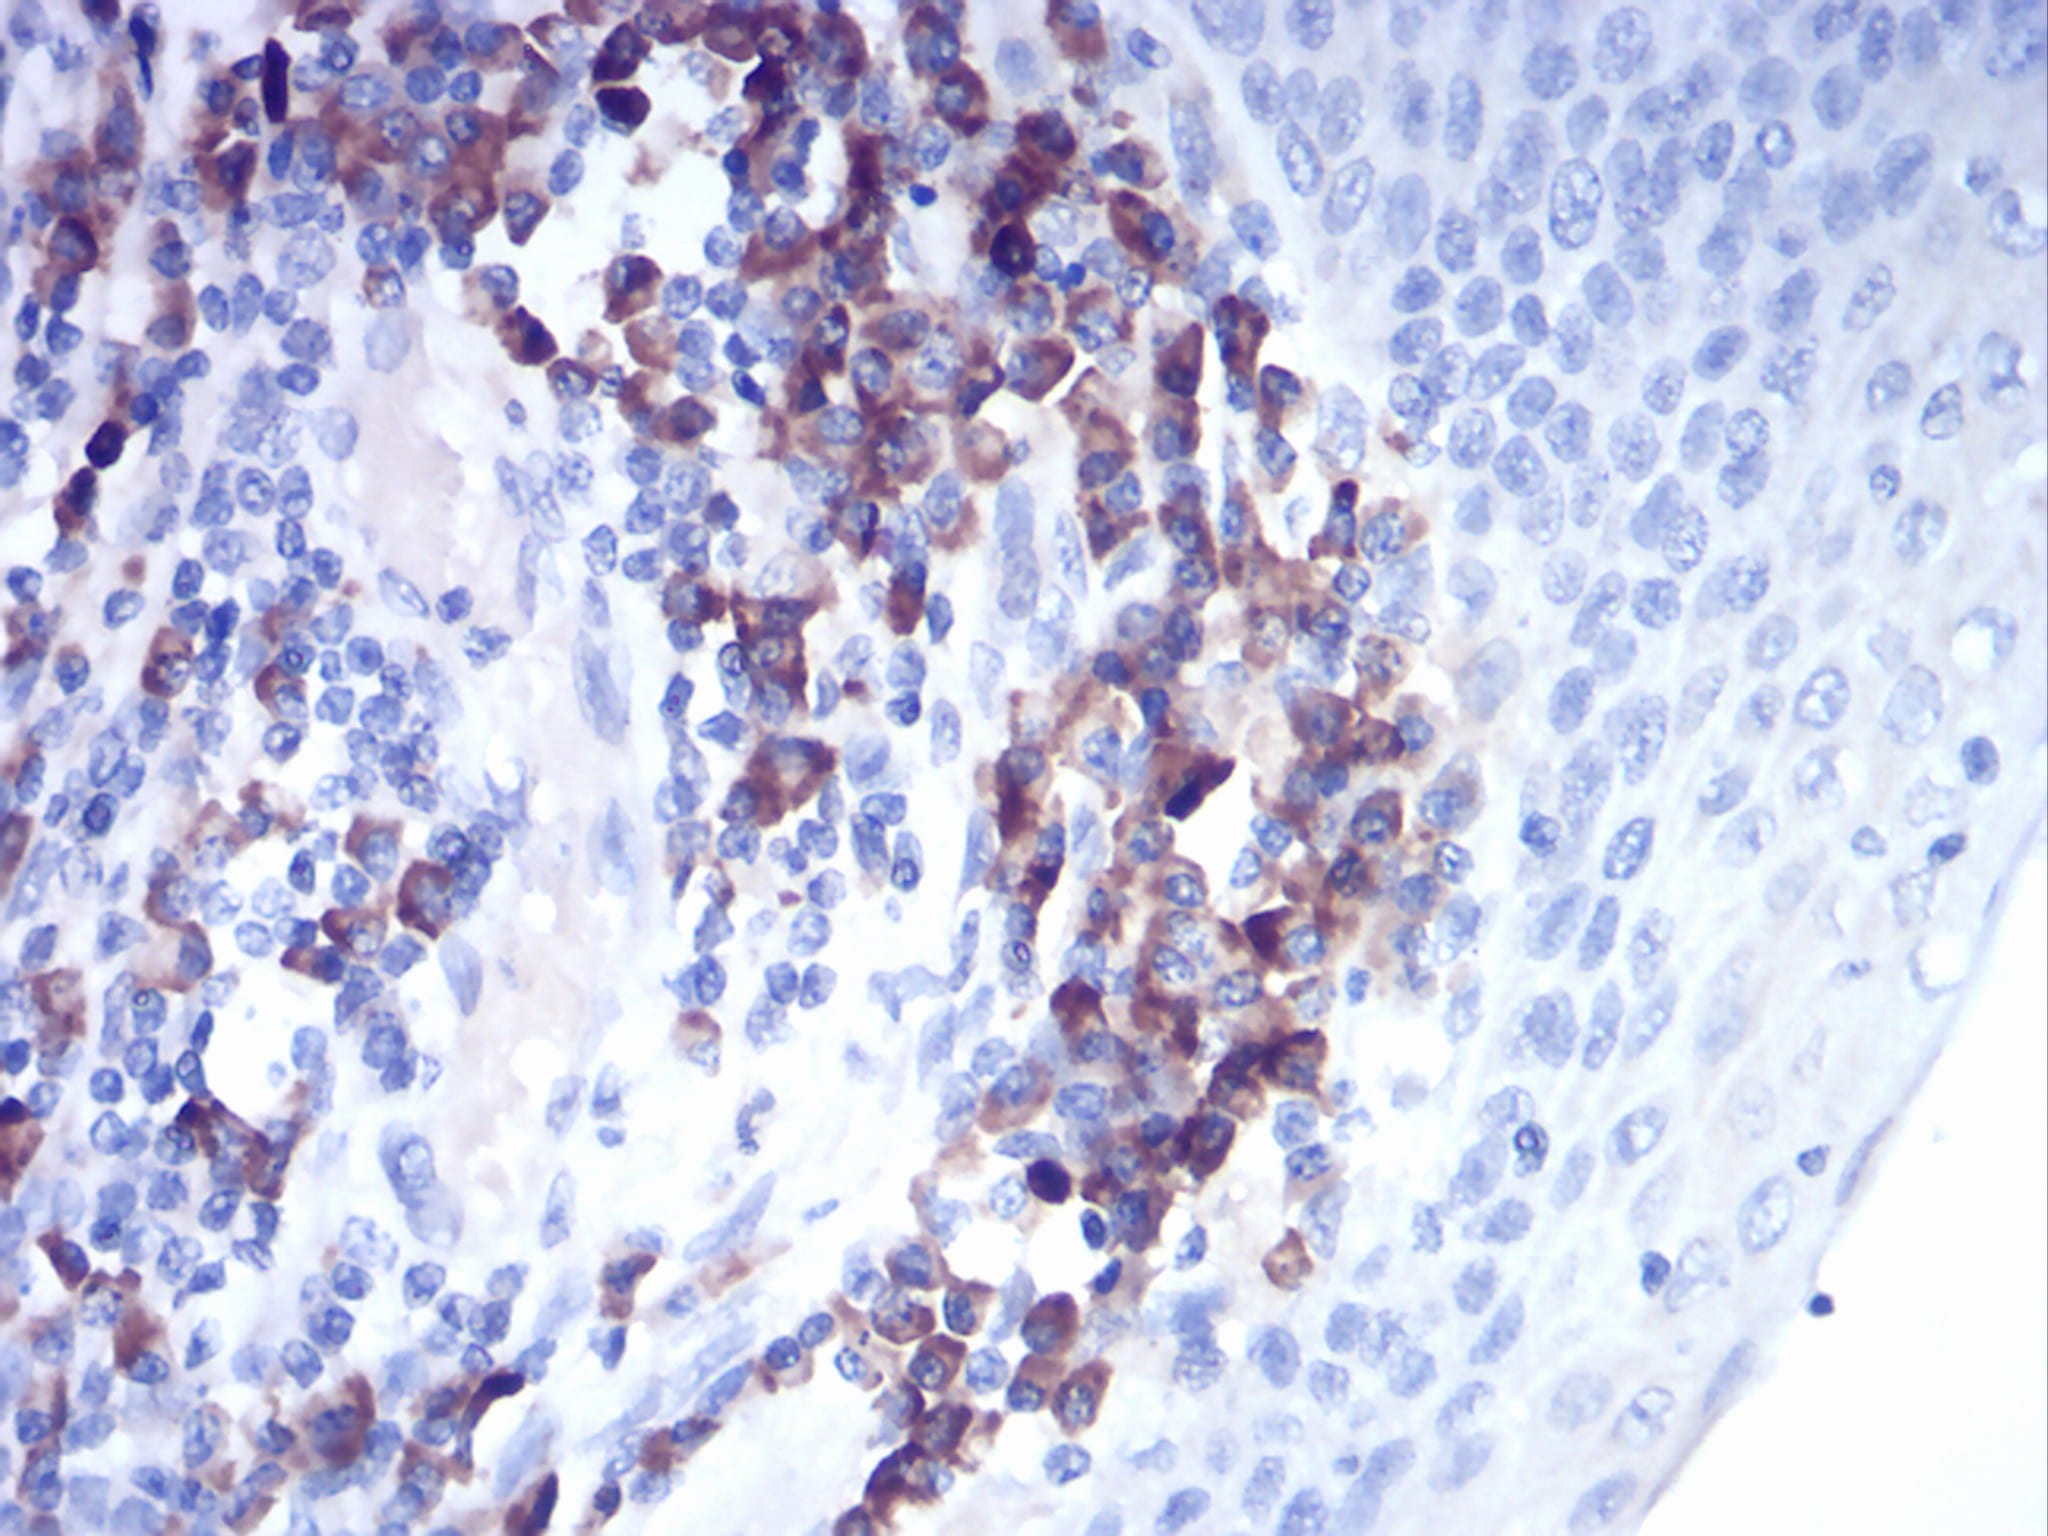

- Immunohistochemical analysis of paraffin-embedded human esophagus tissues using CTSD mouse mAb with DAB staining.